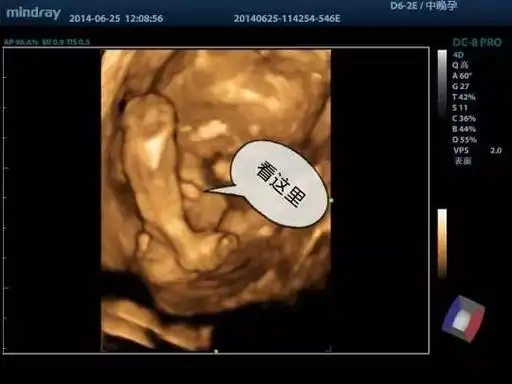

四维彩超,看看是娃还是女子

想知道男女四维彩超就可以帮助你辨别男孩女孩